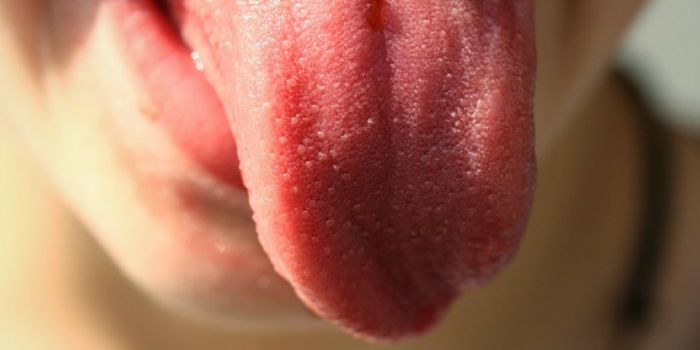

APR 05, 2017CancerThe composition of microorganisms in a person’s mouth could affect more than just their breath and dental health. ...

FEB 15, 2022CardiologySeveral studies have linked oral health and hygiene to longevity.